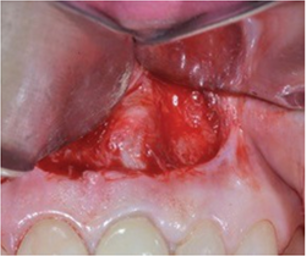

Fig.3 Partch incision for apical lesion exposure

Fig.4 Apicectomy and lesion elimination